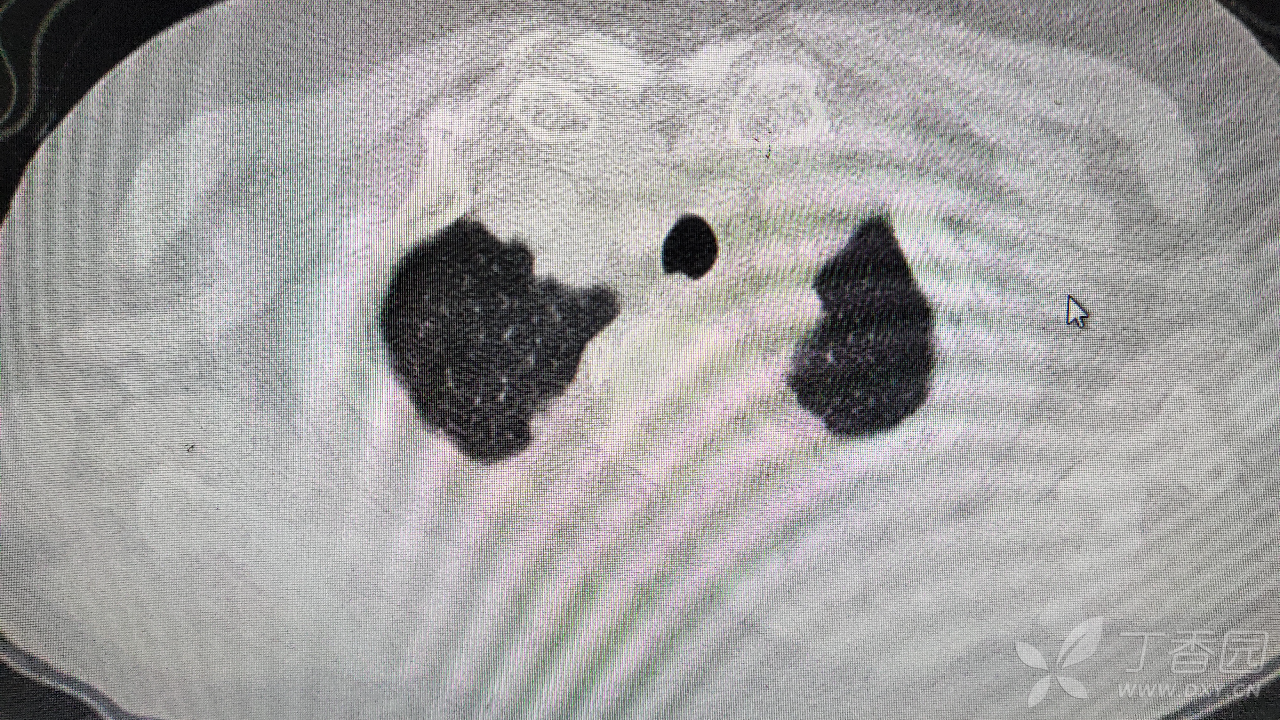

治疗经过:入院后患者仅有乏力,未见明显神经定位征。近期无发热、咳嗽、腹泻症状。遂予血糖、心电图、生化检查及影像检查,结果如下:

心电图将就着看,因为是手机拍的。

我去。。。。。视频只能上传一个,头颅CT上传不了,我直接说报告吧。头颅CT报腔隙性脑梗。